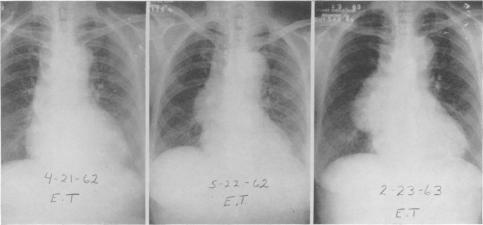

THE SURGICAL TREATMENT OF DISSECTING ANEURYSM OF THE ASCENDING AORTA: WITH A REPORT OF FOUR CASES IN THE CHRONIC STAGE.

Ann Surg. 1964 Jun;159(6):829-45. doi: 10.1097/00000658-196406000-00002.